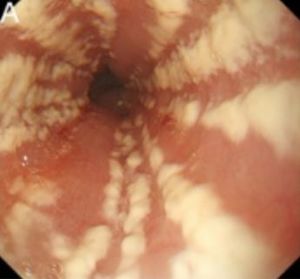

- Thick, white, linear esophageal plaques on endoscopy